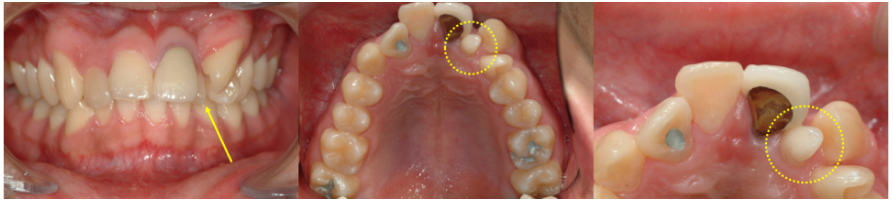

앞니 돌출을 주소로 내원한 20대 남성 사례입니다.

앞니 뒤쪽에서 작은 과잉치가 확인되었으며, 발치 후 치열 정리를 진행했습니다.